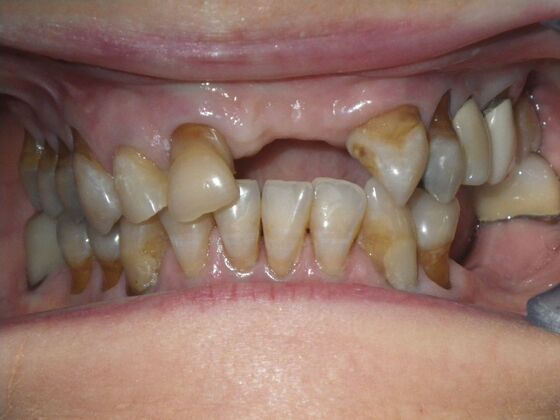

Cosmetic Changes with Veneers and Crown and Bridge: Case 6

Description

This patient had long term acidic erosion of upper and lower teeth eventually leading to loss of upper left central and lateral incisors. While she was somewhat happy with replacement of her front teeth with a removable appliance, she really desired to have something she didn't have to remove. So patient opted to be conservative with two single unit crowns as well as a four unit anterior bridge. These were fabricated using all ceramic without metal